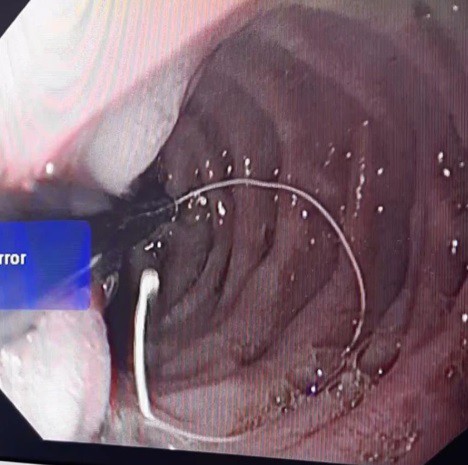

Chiếc kim kèm đoạn cước được các bác sĩ nội soi lấy ra

Các bác sĩ tiến hành nội soi cấp cứu và gắp ra một cái kim khâu kèm theo đoạn chỉ cước dài 25cm nằm ở phần D2 tá tràng. Quá trình thực hiện nội soi chỉ diễn ra trong 6 phút. Sau nội soi cháu được theo dõi trong thời gian ngắn, ổn định về sức khoẻ, các bác sĩ cho cháu xuất viện trong ngày.